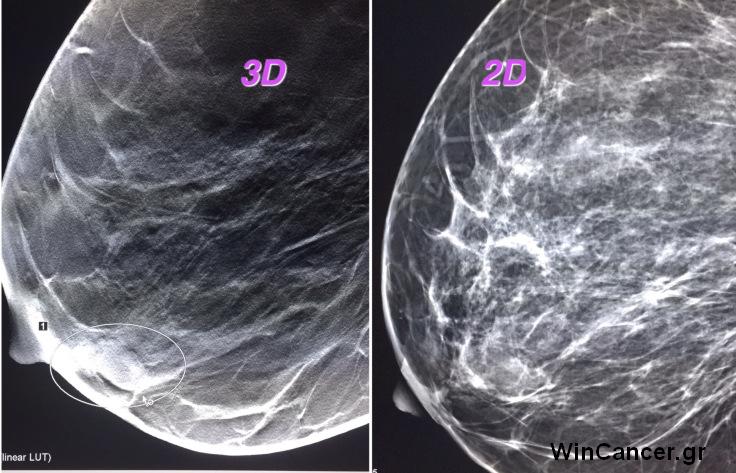

«Είναι σημαντική η σημασία της υπερηχογραφικής εξέτασης με ελαστογραφία αλλά και του τρισδιάστατου υπερηχογραφήματος που μπορεί να πραγματοποιήσει μια γυναίκα σε συνδυασμό με μαστογραφία, προκειμένου να υπάρχει μια ολοκληρωμένη απεικονιστική εξέταση» τονίζει ο Πέτρος Μαλακάσης, Ειδικός Ακτινοδιαγνώστης Μαστού, Διευθυντής του Απεικονιστικού τμήματος Μαστού και Οστεοπόρωσης στην Ευρωκλινική Αθηνών.

Το δίλημμα τρισδιάστατο υπερηχογράφημα ή ελαστογραφία σε ευρήματα σε απλό υπέρηχο, απασχολεί σήμερα πολλούς κλινικούς, αλλά το σωστό είναι κάποιος να χρησιμοποιεί και τις δύο εφαρμογές, προκειμένου να κατηγοριοποιήσει το εύρημα σε παρακολούθηση (κατηγορία 3) ή βιοψία (κατηγορία 4).  Ο συνδυασμός τους με την ψηφιακή μαστογραφία είναι σε θέση να αποκαλύψει κάθε είδους διαφοροποίηση στον μαστό, προλαμβάνοντας στην πλειοψηφία των περιπτώσεων τις καρκινικές αλλοιώσεις.

«Εξάλλου», προσθέτει ο κ. Μαλακάσης, «Για το ίδιο θέμα ο Αμερικανικός Οργανισμός Τροφίμων και Φαρμάκων (FDA), εξέδωσε νέα οδηγία, σύμφωνα με την οποία οι γυναίκες με πυκνούς μαστούς, που σημειωτέον συναντώνται στις μισές περίπου γυναίκες μετά την ηλικία των 40 ετών και όλο και συχνότερα στις νεώτερες ηλικίες, θα πρέπει να ενημερώνονται ότι η μαστογραφία, με την αξιοπιστία του 70% στη συγκεκριμένη περίπτωση, δεν επαρκεί για τη «θωράκισή» τους από ενδεχόμενο καρκίνο του μαστού».